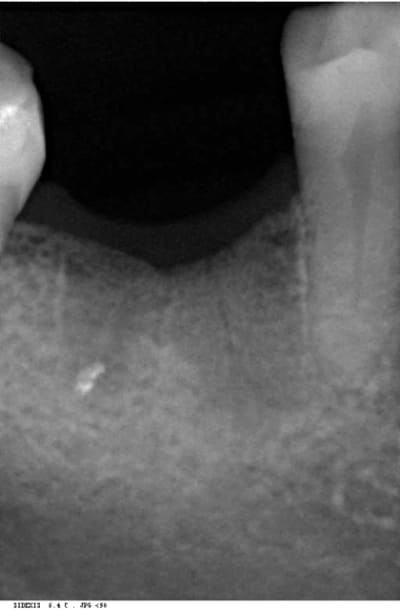

bon les pièces jointes d'alhoun.

décidément aussi nul en endo qu'en internet, et ton implant il est de traviole;)

Trev4 oye2tl - Eugenol

Trev5 lavbuq - Eugenol

Trev1 rgpu7x - Eugenol

Trev2 c5sddm - Eugenol

Trev3 wgcbda - Eugenol

çà doit être une déformation du cliché, regardes bien le premier cliché avec le pilier de cicatisation: on voit bien la partie cylindrique puis l'évasement.